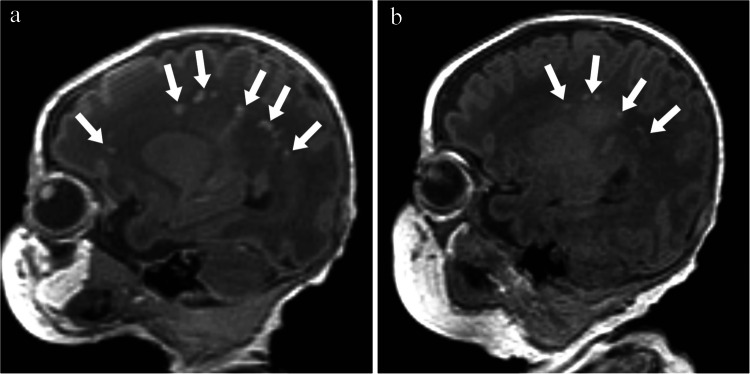

Abstract Image